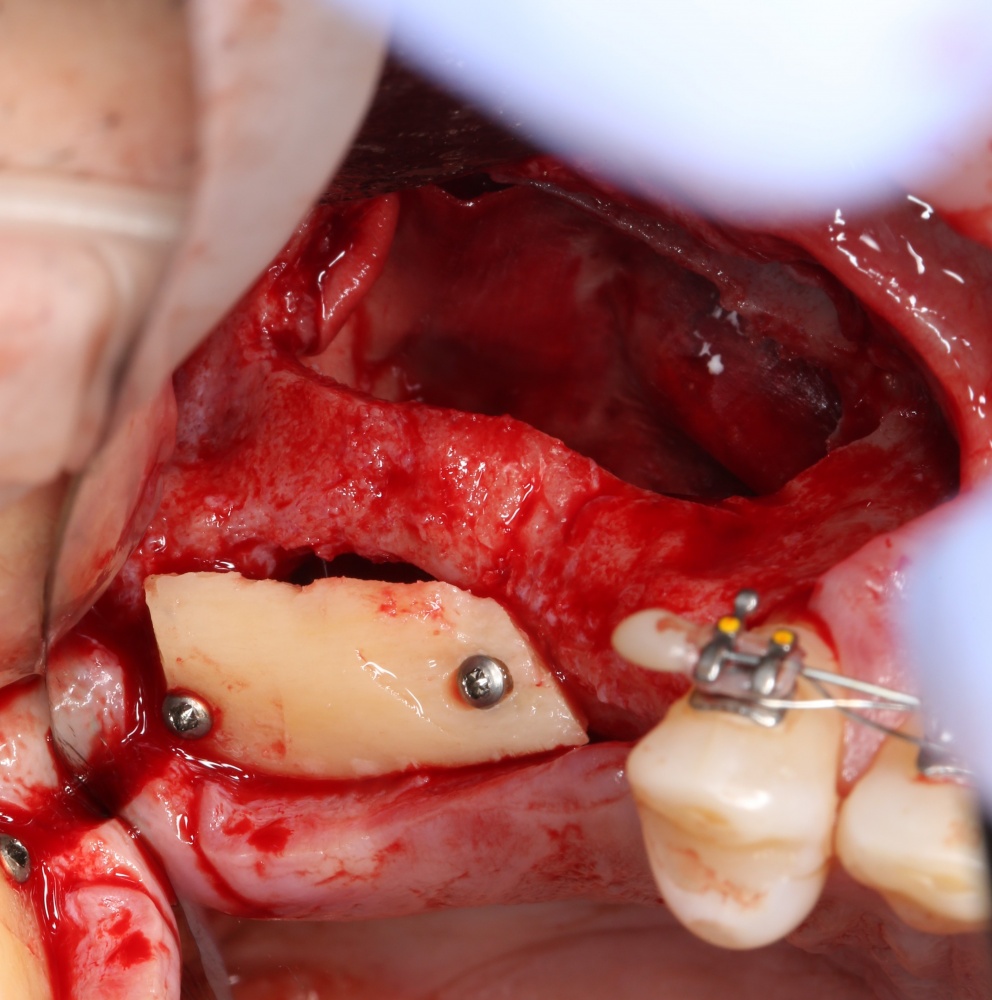

Через 3 месяца — вторая операция — установка имплантата в сформированный объем костной ткани:

Как видите. восстанавливается всё очень легко, никаких дефектов не остаётся, но при этом мы получаем важное преимущество: достаточную свободу движений при формировании субантральной полости и хороший визуальный контроль за состоянием слизистой оболочки. Никакая нажопная оптика или суперпупермикроскоп, к сожалению, не обеспечат подобный контроль при закрытом синуслифтинге. Да, операция получается травматичнее и масштабнее, чем «закрытый» синуслифтинг, но несёт в себе гораздо меньше рисков.